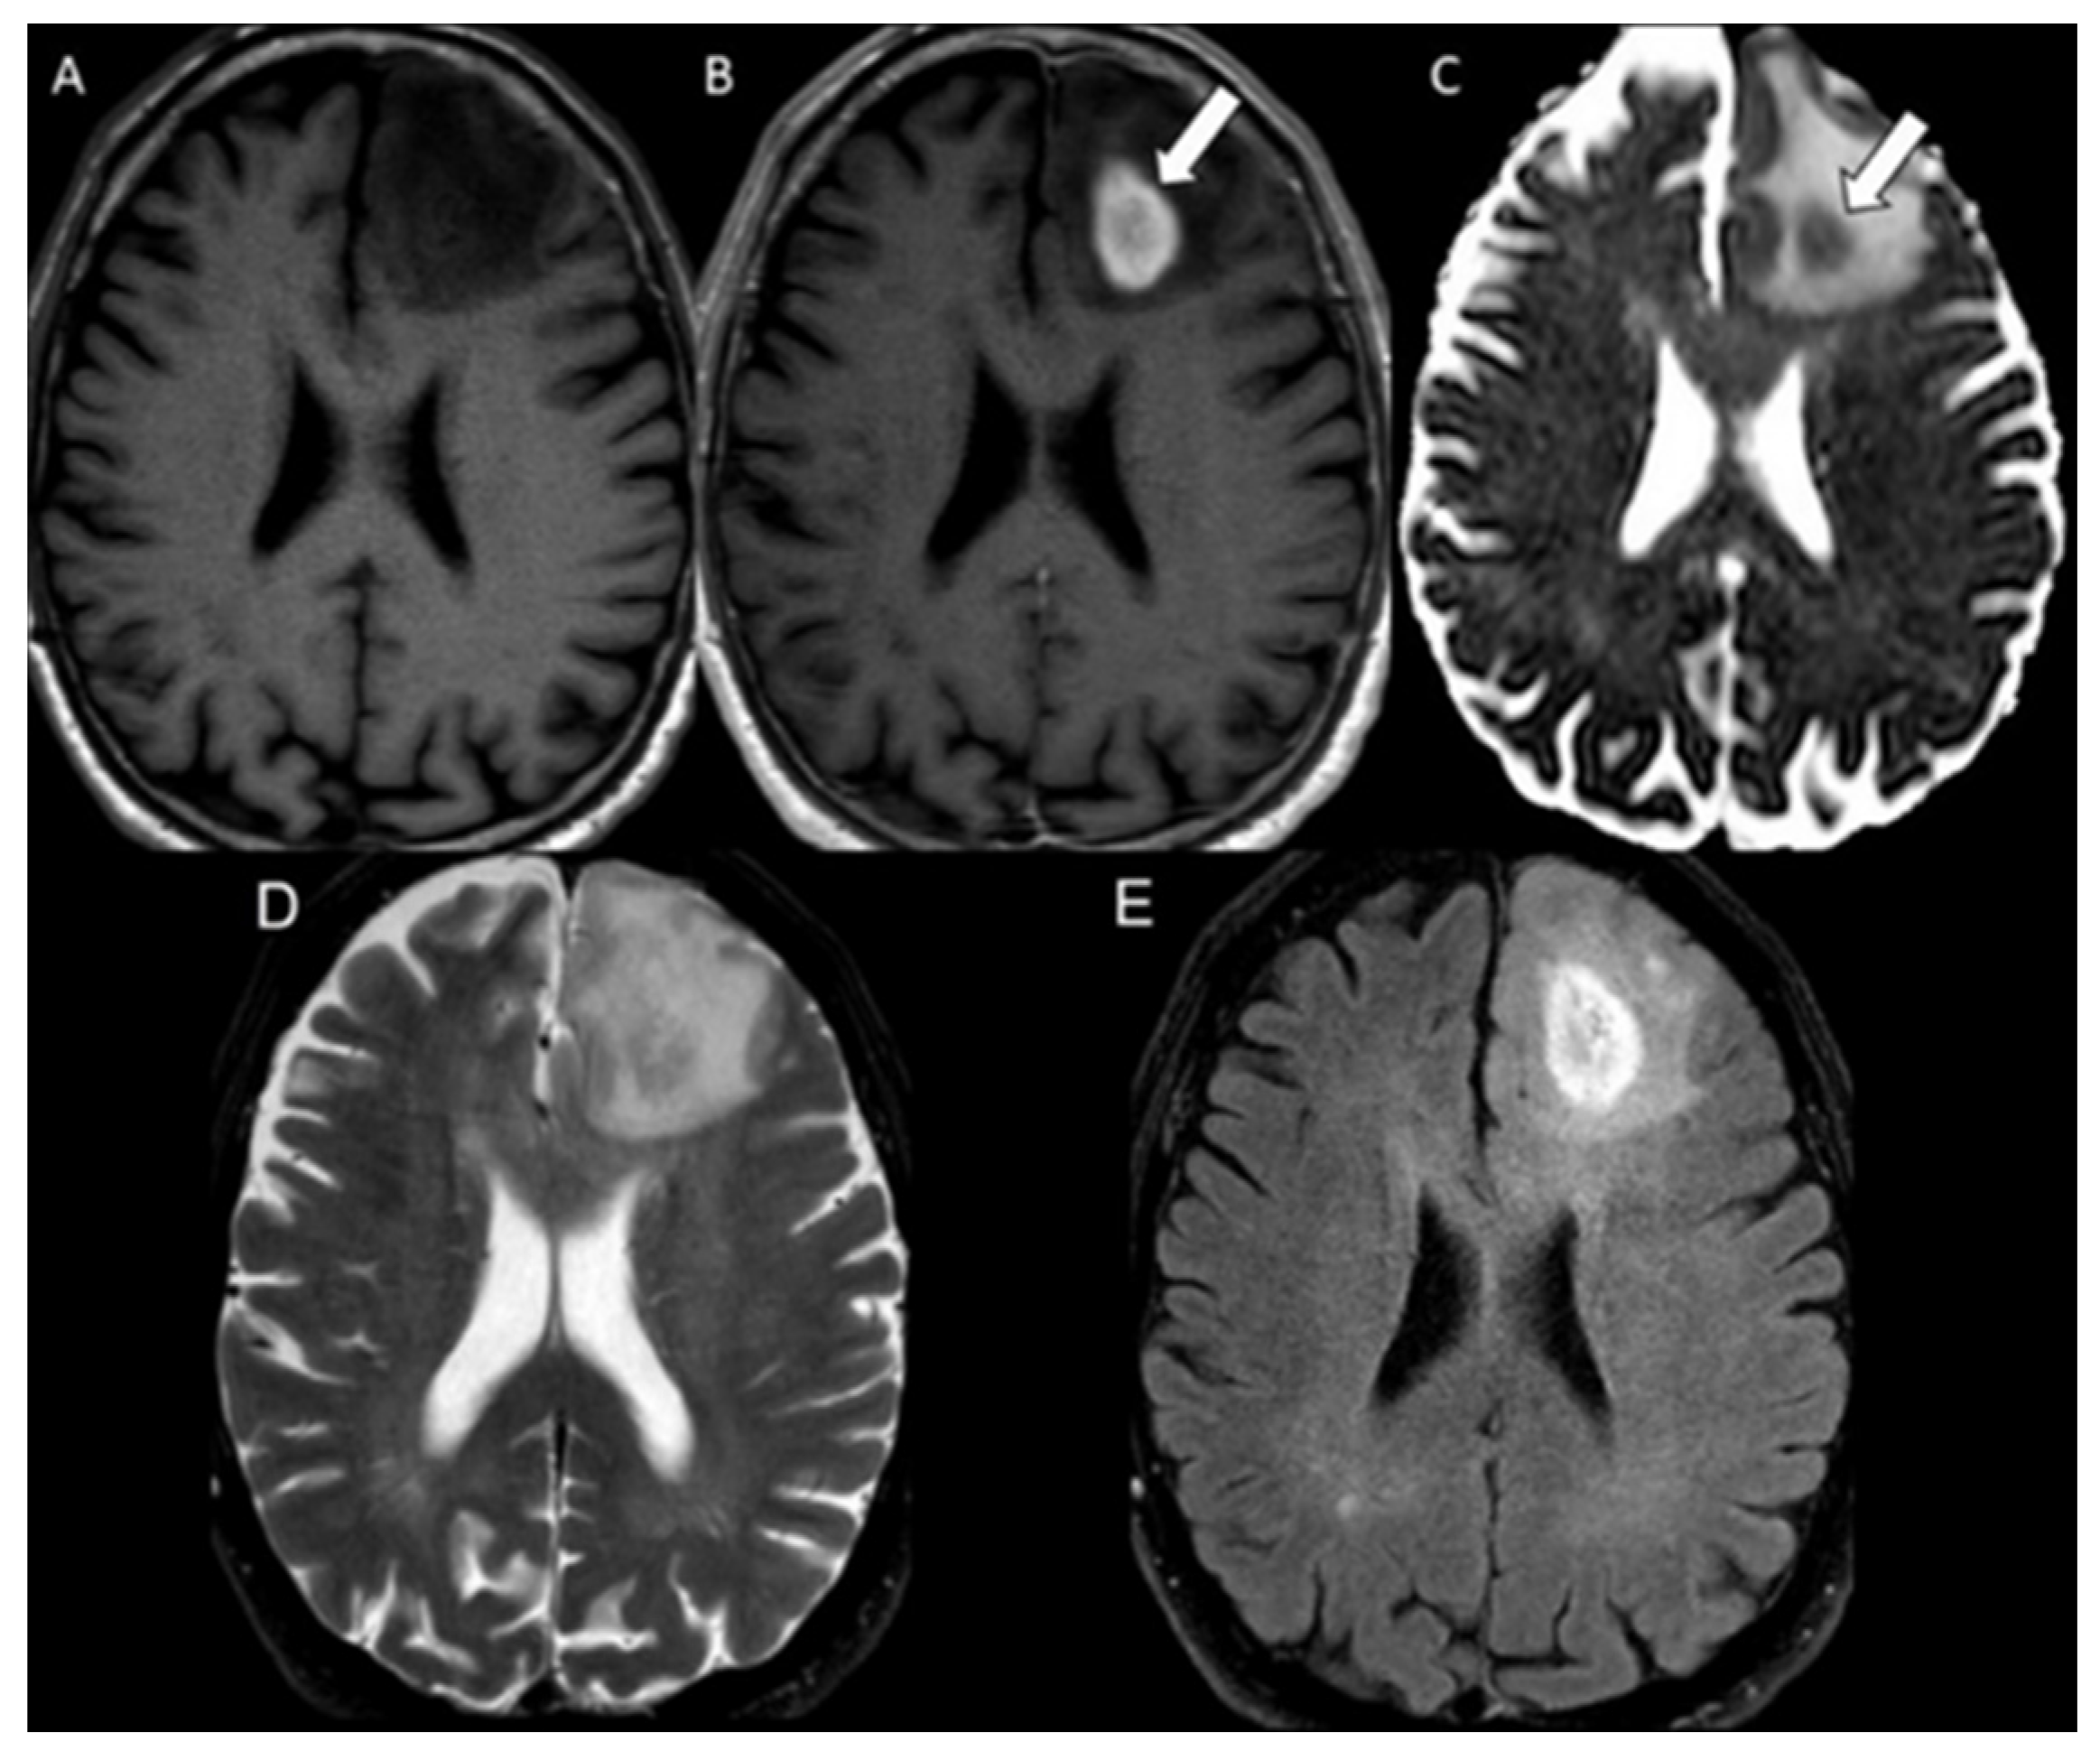

| Radiation necrosis | 58 | 479.0 ± 105.2 | 723.3 ± 64.0 | <0.001 |

| Radiation necrosis | 0.98 | 0.95–1.00 |

| Radiation necrosis | 58 | 0.66 ± 0.14 |